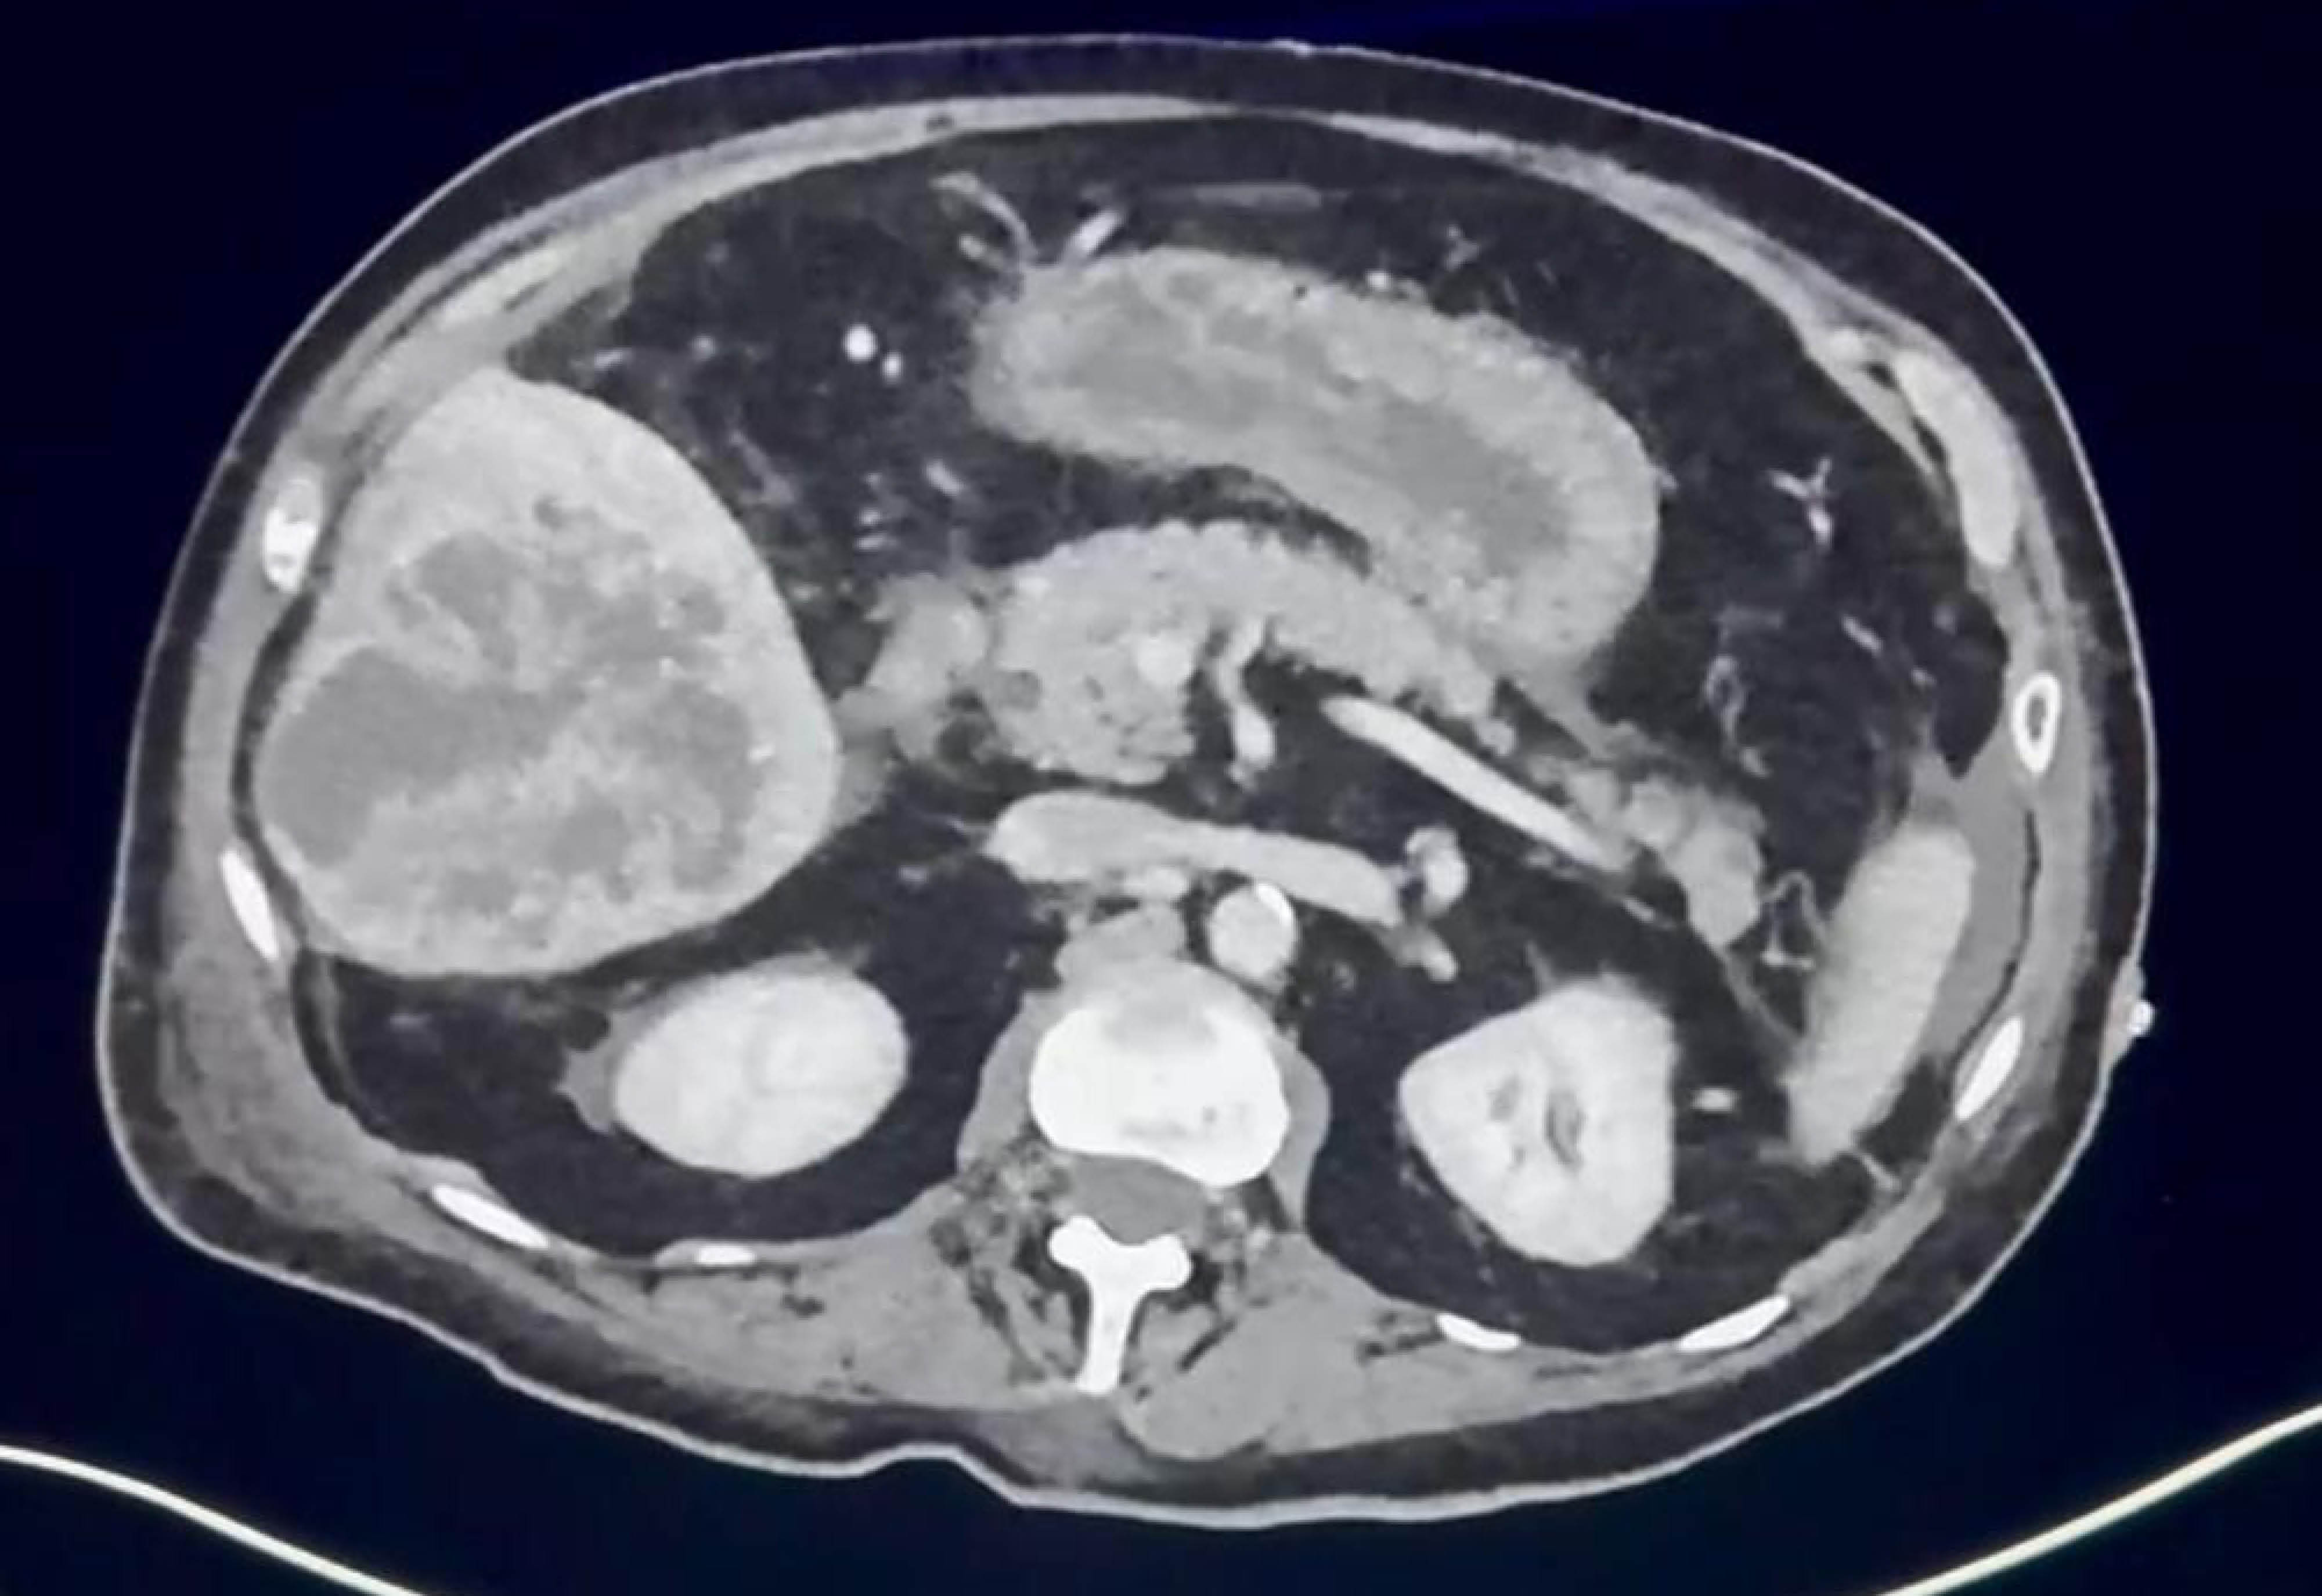

Pyogenic liver abscess caused by hypermucoid Klebsiella pneumoniae

Introduction: pyogenic liver abscess is a collection of pus in the liver caused by invasive bacteria, mainly Klebsiella pneumoniae, including its hypermucoid variant. Case report: an 80-year-old female patient presented with abdominal pain, fever, and general symptoms. The diagnosis was confirmed with imaging tests and laboratory analysis. Treatment included antibiotics and surgical drainage, leading to complete resolution. Conclusion: these abscesses require appropriate management with antibiotics such as cephalosporins or fluoroquinolones and may recur in specific cases. Hypermucoid Klebsiella pneumonia represents a significant epidemiological threat.

Figure 1